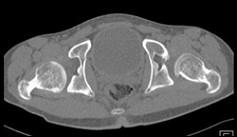

问题 男,23岁,行走跛行,外展受限,两下肢不等长,结合图像,最可能的诊断是 ( )

选项 A、先天性髋内翻 B、髋关节结核 C、髋关节后脱位 D、髋关节前脱位 E、髋关节中心脱位

答案 C